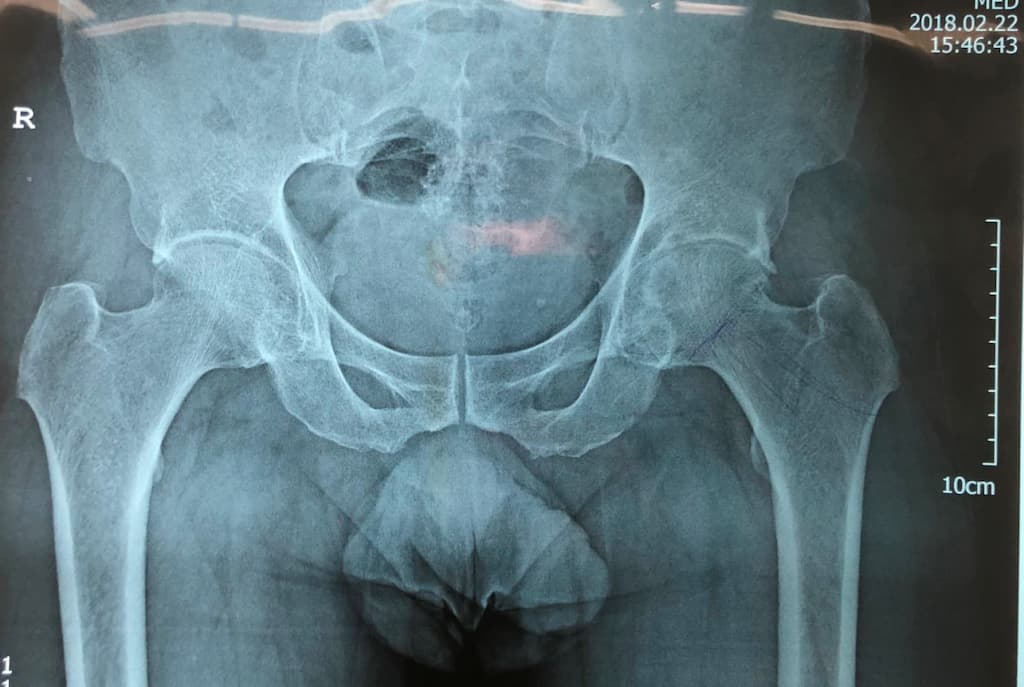

Мэс заслын өмнөх болон дараах рентген зураг

Остеоартрит

Остеоартрит нь ихэвчлэн 50 болон түүнээс дээш насныханд үений мөгөөрсөн эдийн тэжээл, уян чанар , алдагдсанаар үүсдэг өвчин юм. Мөгөөрсөн эдийн гөлгөр гулсамтгай шинж чанар алдагдаж, өвчин даамжирсаар үе хоорондын мөгөөрсөн эдийн бүтэц алдагдан үгүй болж , үе үүсгэж буй яснууд хоорондоо үрэлцэх энэ тохиолдолд хүчтэй өвдөлт үүсдэг. Зарим судлаачид энэхүү өвчнийг удамшилтай холбоотой ч гэж үздэг. Мөн биеийн жингийн илүүдэл, гэмтэл бэртэл, төрөлхийн үений эмгэг, тэнхлэгийн гажиг нь остеоартрит өвчин үүсэхэд нөлөөлдөг.